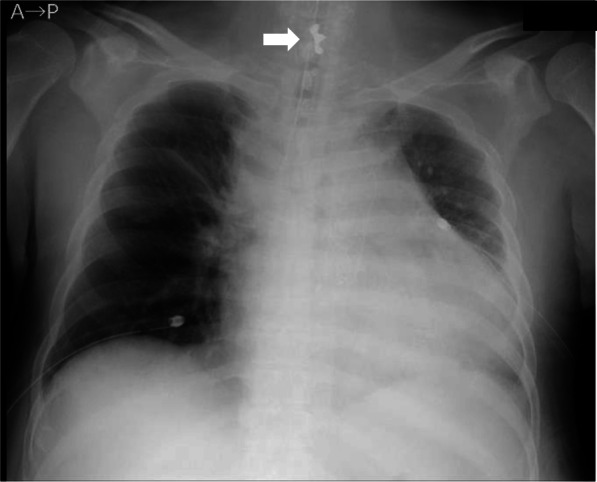

A chest X-ray on POD 34 revealed an abnormal shadow near the larynx (Fig. 1). Review of previous X-ray showed the same shadow in the hypopharynx on POD 19, although it was not identified immediately after arrival in the ICU. A loss of a front tooth was found on POD 22; however, a foreign substance was not confirmed in the oral cavity or on the abdominal X-ray, and the patient was placed under observation. A simple computed tomography (CT) scan on POD 34 showed a shadow with metal artifacts, indicating a crown bridge, outside of the tracheal tube, inside the trachea, and just under the glottis (Fig. 2). Upper esophageal gastrointestinal endoscopy performed on POD 34 also revealed tooth fragments in the stomach. The pharynx and larynx were examined at bedside using McGRATHTMMAC video laryngoscope (Medtronic, MN, USA); however, no foreign matter was found. Observation from the inside of the tracheal tube using the bronchial fiber revealed a foreign body in the trachea just below the glottis, outside (ventral side) the tracheal tube. We therefore considered that the removal of the foreign body in a well-equipped environment would be more suitable than in the ICU and that the foreign body would not cause airway obstruction immediately.

Fig. 1.

A chest radiograph taken on POD 34. A foreign body was confirmed at the midline of the neck (arrow). POD, postoperative day